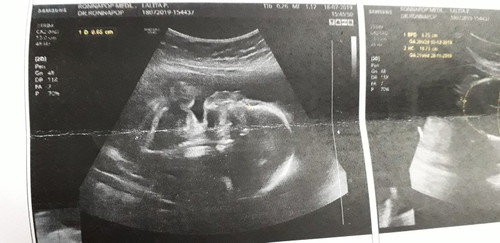

รูปนี้ใช่ส่วนหน้าของน้องไหมค่ะ อยากรู้ว่าจมูกโด่งไหมค่ะ รูปนี้ได้ 22 Week จ้า

กระดูกจะเหนสีขาวเข้มอะแม่